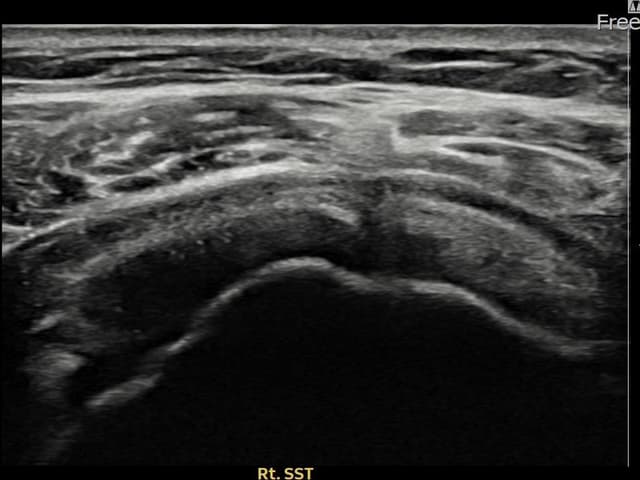

実際の患者様の施術前後の超音波画像。

手術なしで実現できる回復をご確認ください。

[経過期間: 23.08.16~23.10.18]

[縫縮術] 超音波検査にて右 棘上筋腱 関節面側部分断裂(7mm × 3mm (腱厚の約30%欠損))を確認。縫縮術施行後、腱の連続性が回復し、日常生活に復帰されました。